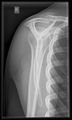

أشعة إكس